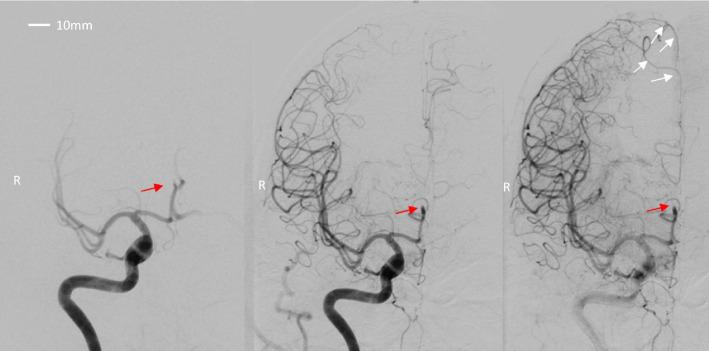

A single patient presenting with limb-shaking TIA underwent CT, Digital Subtraction Angiography, and two different modalities of cerebral perfusion scans: [O]HO PET and [Tc]HMPAO SPECT. Acetazolamide was used in the PET scan to induce vasodilatation, and during the SPECT scan physiological stress, standing up rapidly, was used to induce limb-shaking TIA. CT-angiography and Digital Subtraction Angiography revealed an occlusion in the distal part of the right A2 segment of the anterior cerebral artery, with a corresponding infarction in the watershed area. Collaterals supplied the main vascular territory of the anterior cerebral artery. During rest, neither perfusion modalities demonstrated reduced perfusion outside of the ischemic core. However, we found a pronounced difference between the PET utilizing acetazolamide and the SPECT during the TIA. The PET scan demonstrated relative hypoperfusion in vascular territory supplied by collaterals, while the area around the ischemic core was not affected. Contrary, the SPECT had only minor relative hypoperfusion in the collateral-supplied area, whereas the watershed area proximal to the infarct core had pronounced relative hypoperfusion.

一名出现肢体抖动性TIA的患者接受了CT、数字减影血管造影以及两种不同的脑灌注扫描方式:[O]HO PET和[Tc]HMPAO SPECT。PET扫描中使用乙酰唑胺诱导血管扩张,而在SPECT扫描期间,通过快速站立这种生理应激来诱发肢体抖动性TIA。CT血管造影和数字减影血管造影显示大脑前动脉右A2段远端闭塞,在分水岭区域有相应梗死灶。侧支循环供应大脑前动脉的主要血管区域。在静息状态下,两种灌注方式均未显示缺血核心区以外的灌注减少。然而,我们发现使用乙酰唑胺的PET与TIA期间的SPECT之间存在明显差异。PET扫描显示侧支循环供应区域存在相对灌注不足,而缺血核心区周围区域未受影响。相反,SPECT在侧支循环供应区域仅有轻微的相对灌注不足,而梗死核心近端的分水岭区域有明显的相对灌注不足。